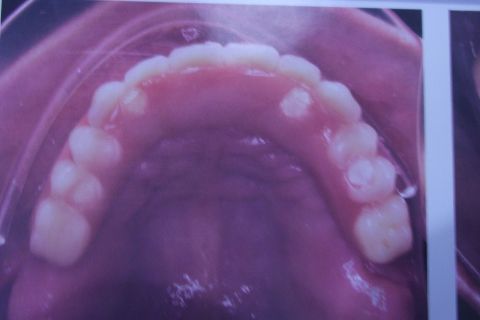

Protocolo Duplo Sendo Superior All-On-4

Caso clínico, 03 de Abr de 2014

Fotos do caso